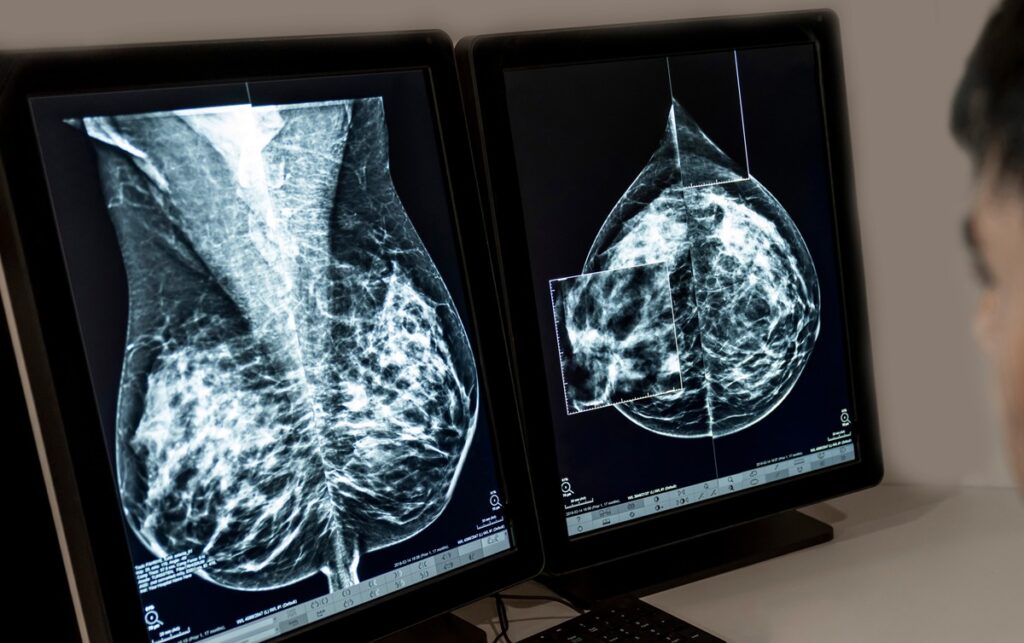

Imagine pequenos pontinhos brancos, como grãos de areia, que aparecem na imagem da sua mamografia. Essas são as calcificações mamárias: minúsculos depósitos de sais de cálcio que se formam nos tecidos da mama.

- Não são visíveis a olho nu nem sentidas no autoexame: Sua detecção acontece quase exclusivamente pela mamografia.